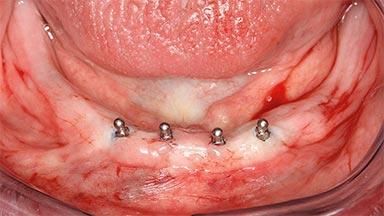

A 74-year-old male patient, a non-smoker, who had been wearing complete dentures for more than 30 years, presented to our clinic complaining about discomfort in connection with his lower denture. The patient suffered from asthma and had a history of cardiac disease and blood pressure disorders. All conditions were medically controlled and stable. The clinical inspection of the oral cavity revealed an ill-fitting complete mandibular denture. The patient expressed the wish for his lower denture to “stop moving when chewing, swallowing, and speaking.” He reported having heard about dental implants and asked whether these could help in “fixing” his lower denture, but also requested non-invasive treatment. The mucosa presented healthy and was free of defects such as pressure sores. An band of keratinized mucosa approximately 2 mm wide was visible. The patient’s mucosal biotype was medium thick to thin.